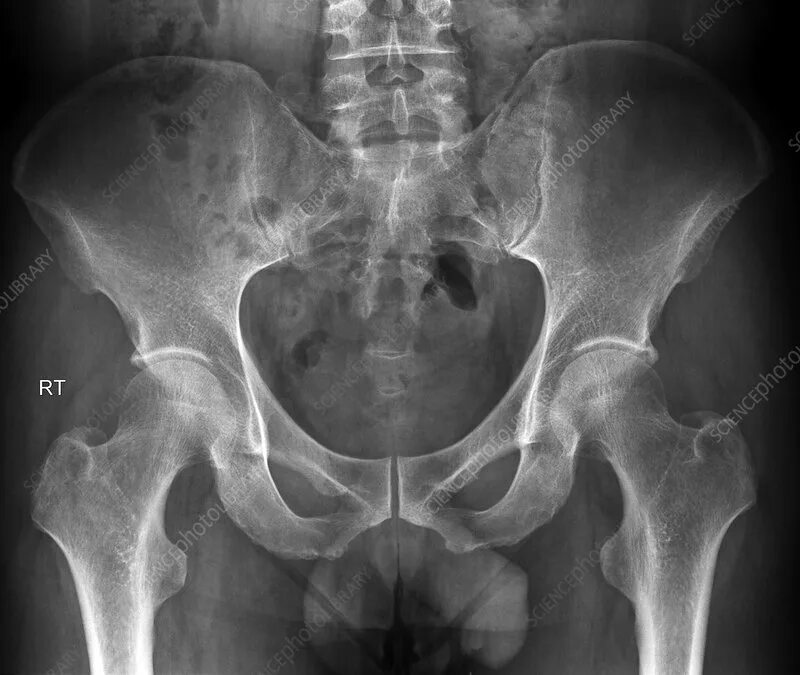

Вывих тазобедренного у взрослых